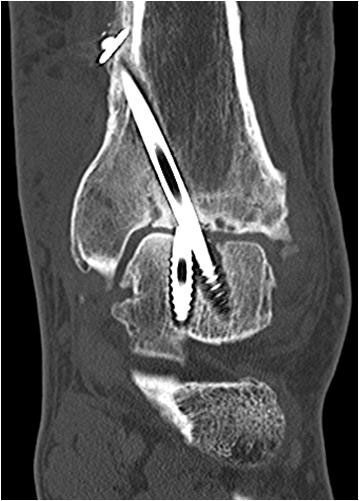

• Primäre oder posttraumatische Arthrose des OSG und USG (Abbildung 1, Abbildung 2).

• Revision einer gescheiterten Fusion des OSG/ USG (Abbildung 3, Abbildung 4).

Implantation des Nagels und BV-Kontrolle (Video 5). Schließlich erfolgt die Verriegelung des Nagels über entsprechende Zielvorrichtungen. Bei einigen Nageltypen gibt es nageleigene Kompressionsmechanismen, die eine zusätzliche Drucksteigerung im Bereich der Arthrodeseflächen des ehemaligen oberen und unteren Sprunggelenkes erlauben (Video 6). Die abschließende BV-Kontrolle in beiden Ebenen sollte eine regelrechte Stellung der Arthrodese mit 90° - Stellung im Rückfuß, in der anderen Ebene mit einem Rückfußvalgus von ungefähr 5° zeigen.